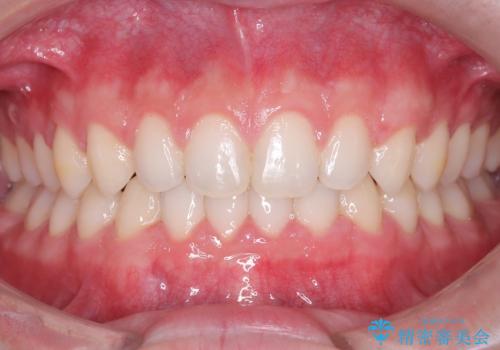

- 主訴:上の歯列の空隙を閉じたい

上顎前歯部に空隙が目立ちました。ワイヤー矯正、インビザライン(マウスピース矯正)どちらの方法でも適用症例と説明し、ワイヤー矯正治療(審美装置)を希望されました。

上顎歯列の空隙を閉じるのと一緒に、ディープバイト気味の被蓋も下顎前歯の圧下を行い改善しました。

矯正治療期間:2年ちょうど